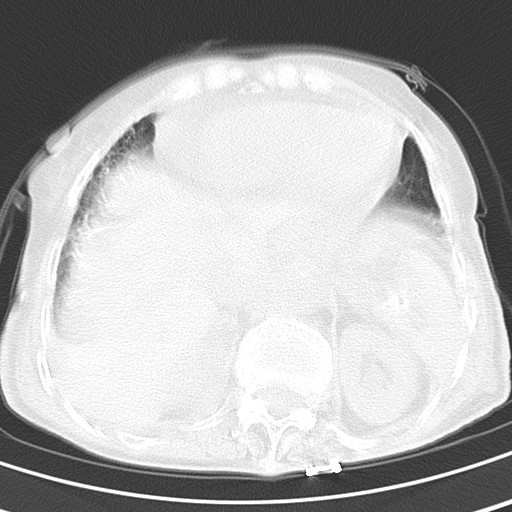

标题: CT21467:女,93岁,摔伤后检查。

女,93岁,摔伤后检查。

右肺炎症,心功能不全伴双侧胸腔积液,右下肺膨胀不全,食管裂孔疝,冠脉钙化,心包少量积液,左侧肋骨骨折,请上传骨窗.

右侧锁骨\\肩胛骨骨折、右侧湿肺,心功能不全伴双侧胸腔积液,右下肺膨胀不全,左膈破裂或食管裂孔疝,冠脉钙化,心包少量积液,请上传骨窗.

右肺炎症,心功能不全伴双侧胸腔积液,右下肺膨胀不全,食管裂孔疝,冠脉钙化,心包少量积液,左侧肋骨骨折,右肩甲骨粉碎性骨折。93岁,高寿哇!

右肺炎症,心功能不全伴双侧胸腔积液,右下肺膨胀不全,食管裂孔疝,冠脉钙化,心包少量积液,左侧肋骨骨折,右肩甲骨粉碎性骨折。